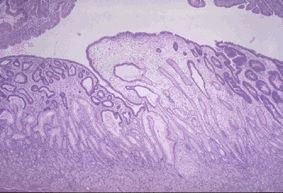

A case of gastric juvenile polyposis with multiple cancers.

Tokyo Pref., Cooperative study between National Cancer Center and Kyushu Cancer Center

Tumor-like lesions/Juvenile polyposis

Stomach/Other

Histology